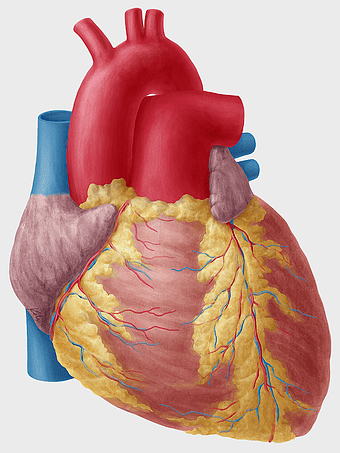

Heart Anatomy Diagram, human heart drawing, realistic heart illustration, cardiovascular system, medical illustration, organ structure, human anatomy study -

human heart anatomy, cardiovascular system illustration, medical heart diagram, heart organ structure, human body organ visuals, anatomical heart drawing, heart health -

human heart anatomy, cardiac muscle illustration, circulatory system model, heart health visual, cardiovascular organ diagram, medical heart image, visceral structure depiction -